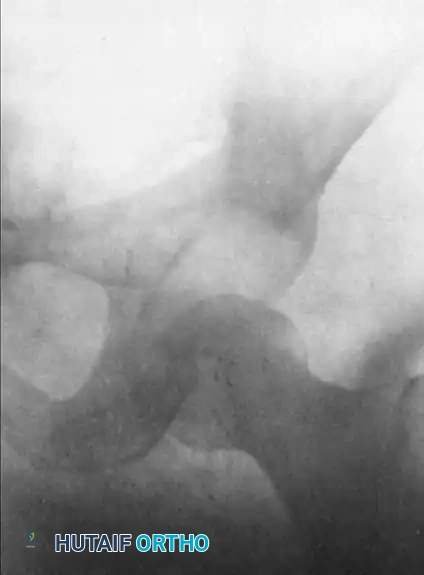

4. Radiographic Monitoring: Anteroposterior (AP) radiographs of the pelvis are obtained on alternate days to monitor the descent of the femoral head.

Image

FIGURE 61-3 A: Anteroposterior radiograph of the left hip in a 27-year-old man, illustrating a chronic posterior dislocation with early myositis ossificans, presenting 37 days after the initial injury.

1. Descent of the Femoral Head: Usually, by the fifth day of continuous 18 kg traction, the femoral head will have been pulled distally to a level at or slightly below the superior rim of the acetabulum.